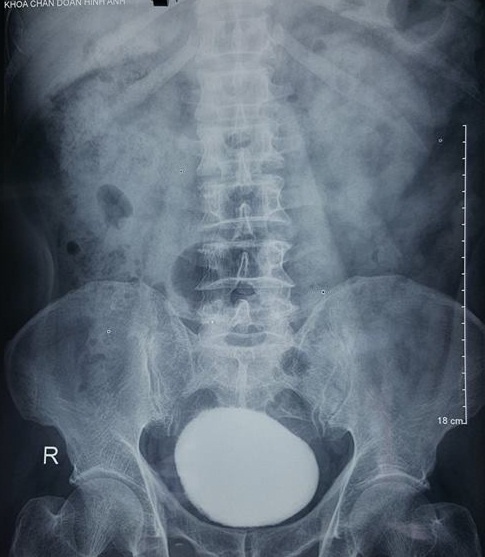

| Hình ảnh chụp X-quang viên sỏi của bệnh nhân Xuân. Ảnh: Thanh Xuân.

Kết quả siêu âm cho thấy bệnh nhân bị sỏi bàng quang có kích thước lớn. Qua phim chụp X-quang, hình ảnh sỏi cản quang vùng tiểu khung chiếm gần hết thể tích bàng quang của người bệnh.